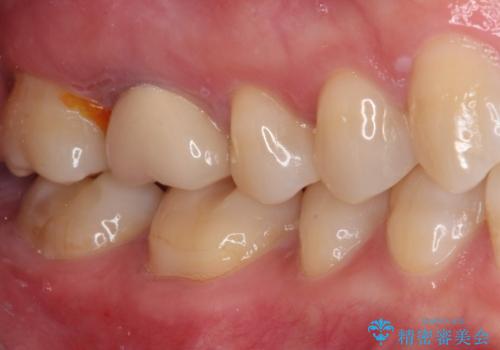

- 上下の奥歯に違和感を感じ、近医にて虫歯を指摘されたとのことで来院された患者様です。

診査したところ、下顎の奥歯は膿の出口ができており、上顎の奥歯は噛んだときに痛みを感じている状態でした。

まずは根管治療を行い、症状が落ち着いたことを確認して、オールセラミッククラウンにて補綴治療を行うこととしました。